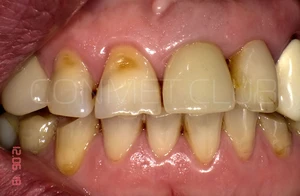

Фото этой же коронки через 15 лет после операции.

Вид на палатинальную поверхность.

15 лет полноценной функциональной нагрузки.